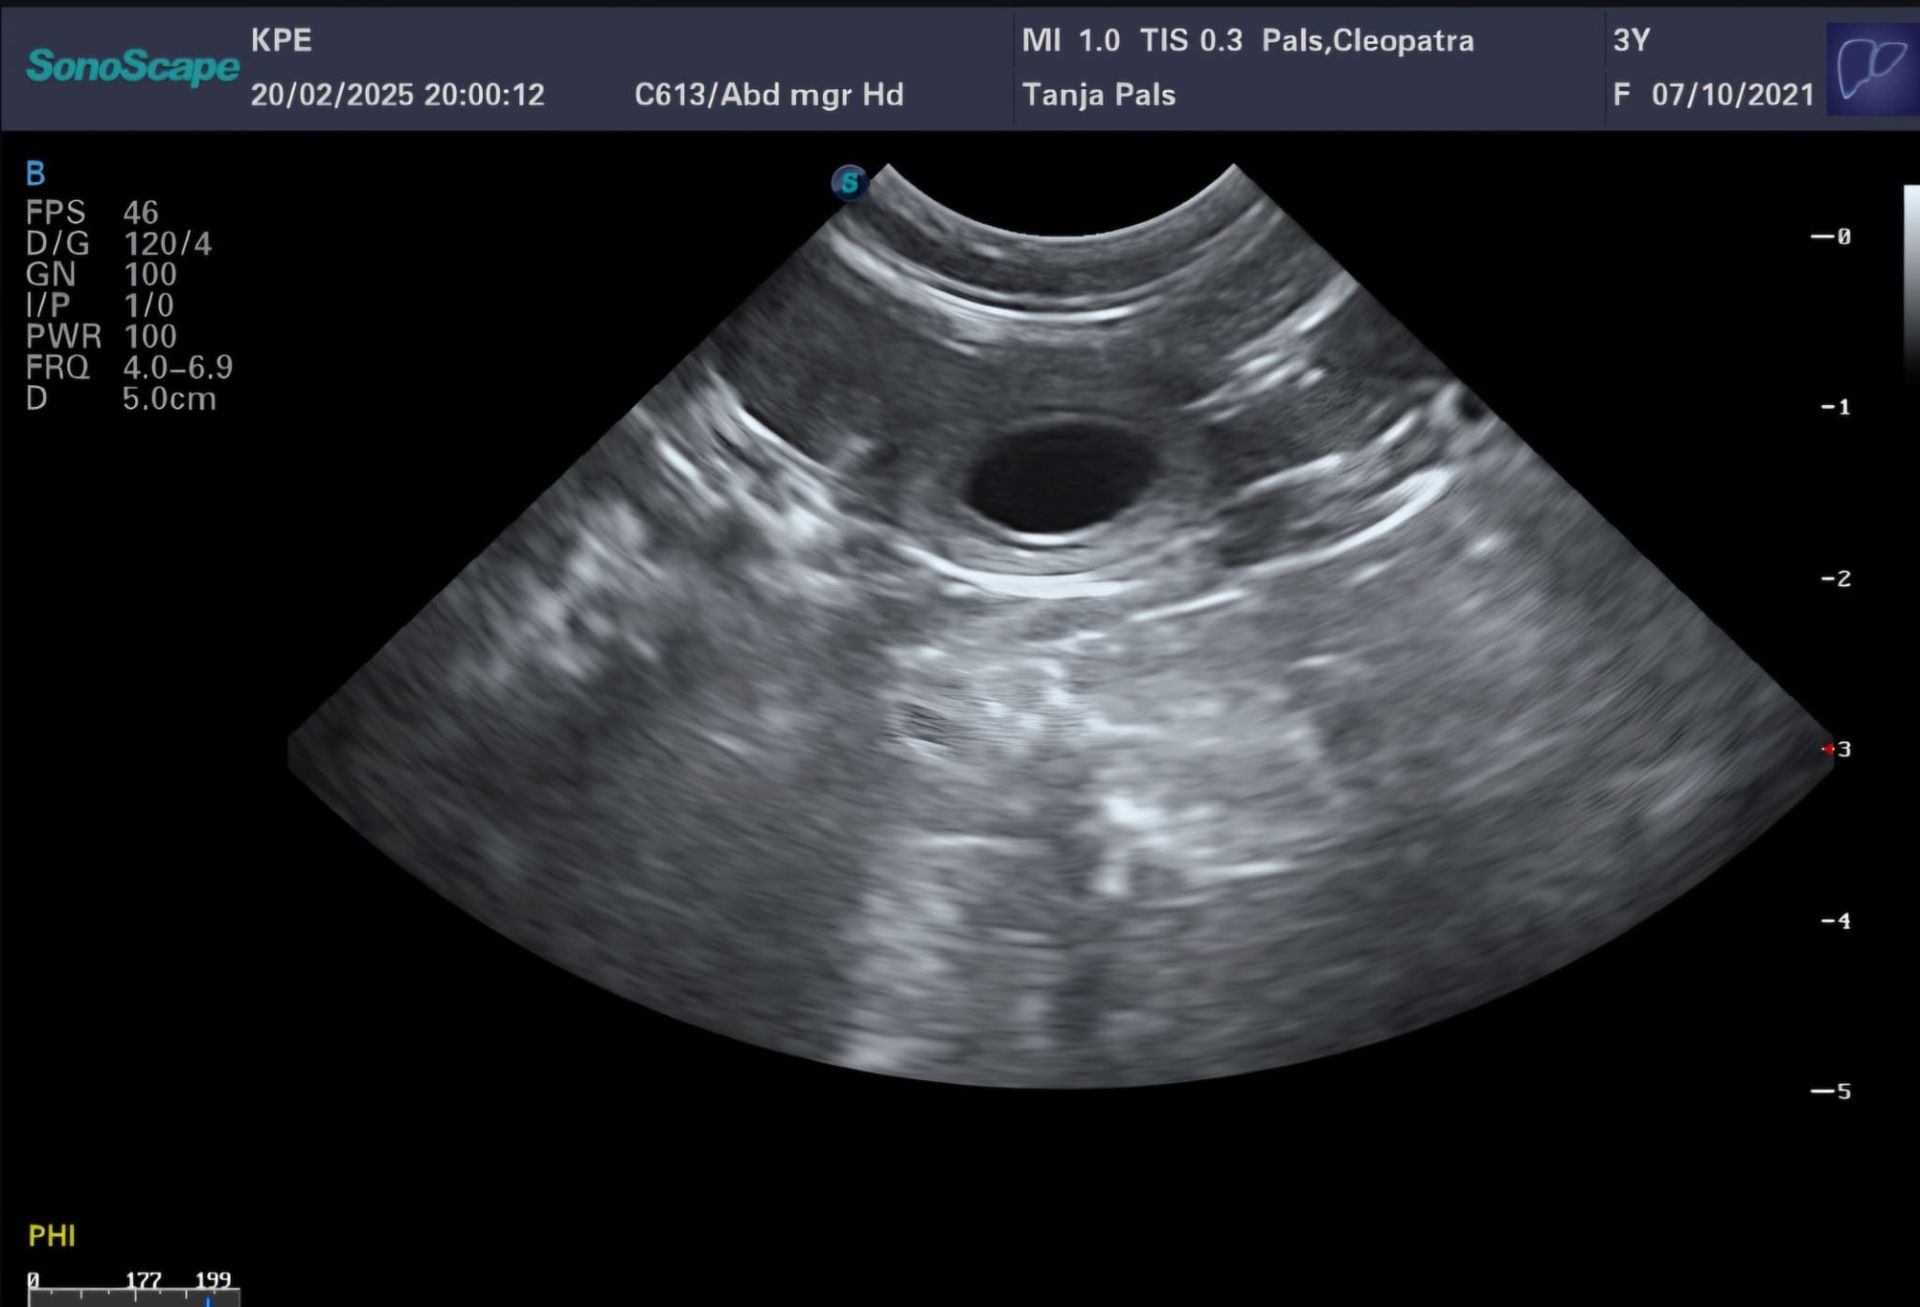

20.02.2025 schon der 24.Tag von etwa 63. Die Ultraschalluntersuchung zeigt es gibt gut erkennbare Fruchthüllen. Cleopatras Herz schlägt kräftig. Der Puls ist super. Cleopatra zeigt eine erhöhte Durchblutung. Super Voraussetzung um die Embryos fest in der Gebärmutter aufzunehmen. Wir sind sehr glücklich, da wir jetzt wirklich trächtig sind.